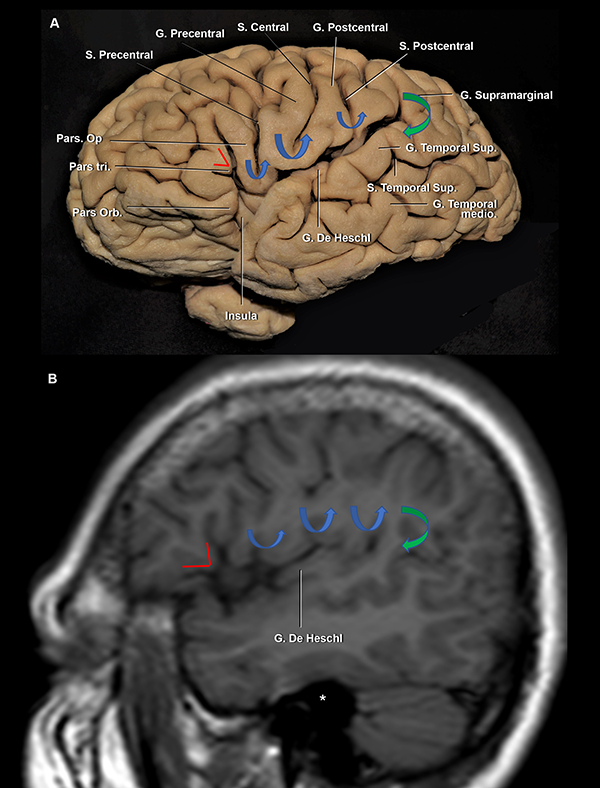

Figura 5: A. Vista lateral de un hemisferio cerebral izquierdo. B. RMN, secuencia T1, corte sagital. La pars triangularis tiene forma de “V” (líneas rojas). Luego, encontramos 3 giro con forma de “U” (flechas azules), de anterior a posterior: 1) pars opercularis; 2) giro subcentral; y 3) la conexión entre los giros postcentral y supramarginal. Finalmente, la flecha verde marca la conexión con forma de “C” entre los giros supramarginal y temporal superior. Se observa al giro de Heschl enfrentado al postcentral. Ambos se encuentran en el mismo plano coronal que el CAE. Asterisco: proyección medial del CAE. S: surco; G: giro; Sup: superior; inf: inferior.

El giro frontal inferior se divide por los ramos superficiales de la FS, de anterior a posterior, en la pars orbitalis, la triangularis y la opercularis (Figura 3 y 5A).

La pars triangularis, que posee una forma de “V”,22,23 suele albergar un ramo originado del surco frontal inferior y cubre al ápex insular. Por otro lado, la pars opercularis, que tiene forma de “U”,22 alberga un ramo originado del surco precentral, o en su defecto, al extremo inferior del surco precentral (Figura 3 y 5). La pars opercularis, se recuesta superficialmente sobre el giro corto posterior de la ínsula (Figura 4A). Más aún, la rodilla de la cápsula interna y el foramen de Monro se ubican en la profundidad de dicho giro corto (Figura 12B). Finalmente, el área de Broca del lenguaje, se compone de la pars triangularis y opercularis del hemisferio dominante.22

El lóbulo central se localiza posterior a la pars opercularis y se compone de los giros pre y postcentral.18,22 El puente neural que conecta dichos giros en el extremo inferior del surco central es el giro subcentral, también denominado pli de passage frontoparietal inferior de Broca u opérculo rolándico (Figura 4A y 5A).22,23 El giro precentral se recuesta superficialmente sobre el tercio medio de la corteza insular y el cuerpo de los ventrículos laterales. El surco central corre en una dirección paralela al surco central de la ínsula. Está reportado en la literatura que hasta en el 84% de los casos, el surco no se extiende hasta contactar la FS, en consonancia con nuestros hallazgos.12,18 El giro postcentral se ubica superficial al tercio posterior de la ínsula (Figura 4A y B).

La parte más posterior del techo de la fisura silviana la conforma el giro supramarginal, que alberga al ramo terminal ascendente de la fisura silviana. El opérculo supramarginal envuelve al punto silviano posterior, conectando a los giros supramarginal con el temporal superior (Figura 3 y 5). En la profundidad del margen más anterior del giro supramarginal es encontrado el punto insular posterior, que marca a su vez el extremo posterior del lóbulo insular (Figura 6). Asimismo, el extremo posteromedial del giro de Heschl se localiza justo posterior al punto insular posterior (Figura 12B).

El plano temporal está compuesto por dos o tres giros transversos. Es un área de forma triangular cuyo ápex apunta hacia el atrio ventricular. El giro de Heschl y la parte posterior del giro temporal superior constituyen el área auditiva primaria (Figura 6A, 10A y B).22 En su extremo anterolateral, el giro de Heschl se encuentra en el mismo plano coronal que el giro postcentral. Además, se evidenció que el giro de Heschl a su vez se encuentra en el mismo plano que el conducto auditivo externo (CAE) (Figura 5). En el plano coronal, tiene una orientación horizontal, haciendo que la disección de la fisura en esta área sea más dificultosa.